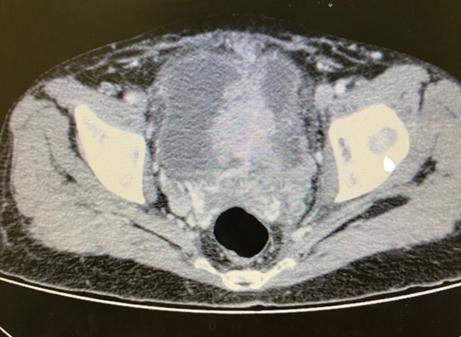

The abdominal image showed enlargement of the left kidney with a solid, expansive lesion that exhibited irregular contours and heterogeneous contrast enhancement, measuring 6.4cm along its longest axis, with involvement of the ureter and gonadal vein. In the pelvis, an extensive, expansive formation was identified in the bladder with a vegetative and infiltrative aspect, with uptake similar to that associated with renal injury and signs of invasion of the abdominal wall and pubic bones (Figures 1,2).

Figure 2 Computed tomography image of an infiltrative mass in the bladder.